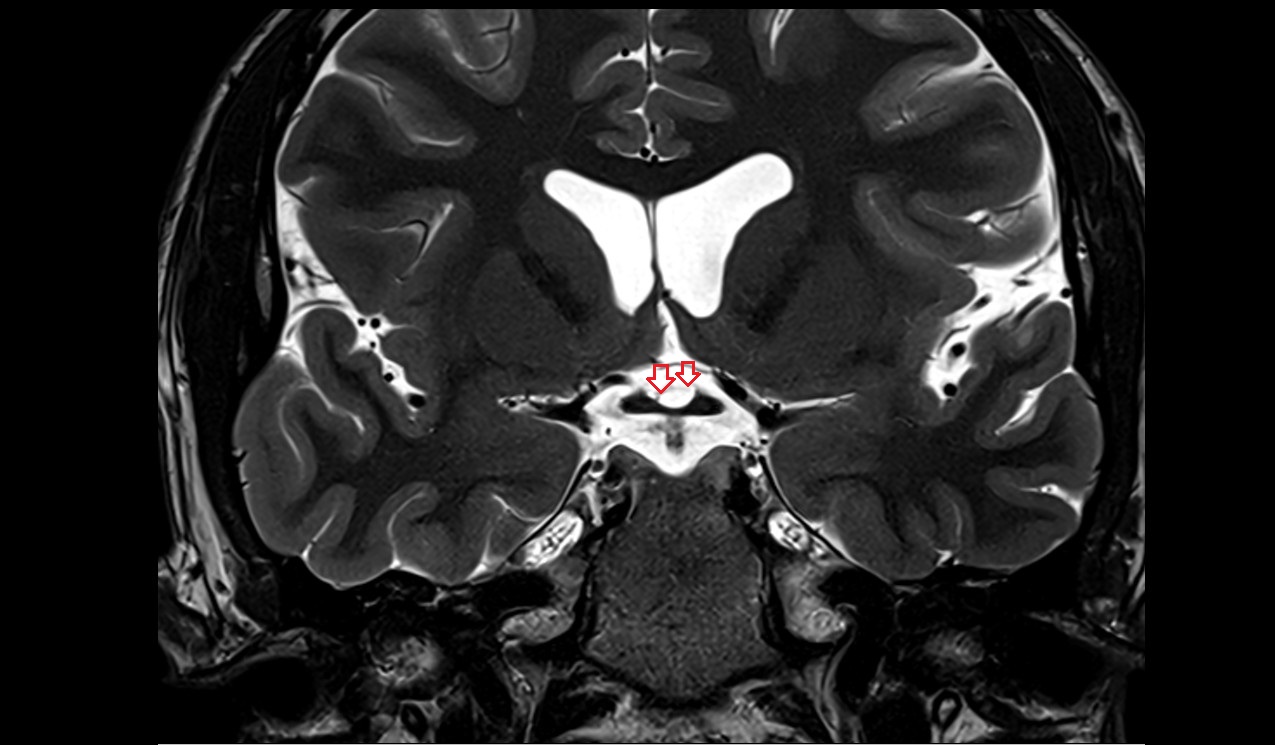

- Pituitary stalk